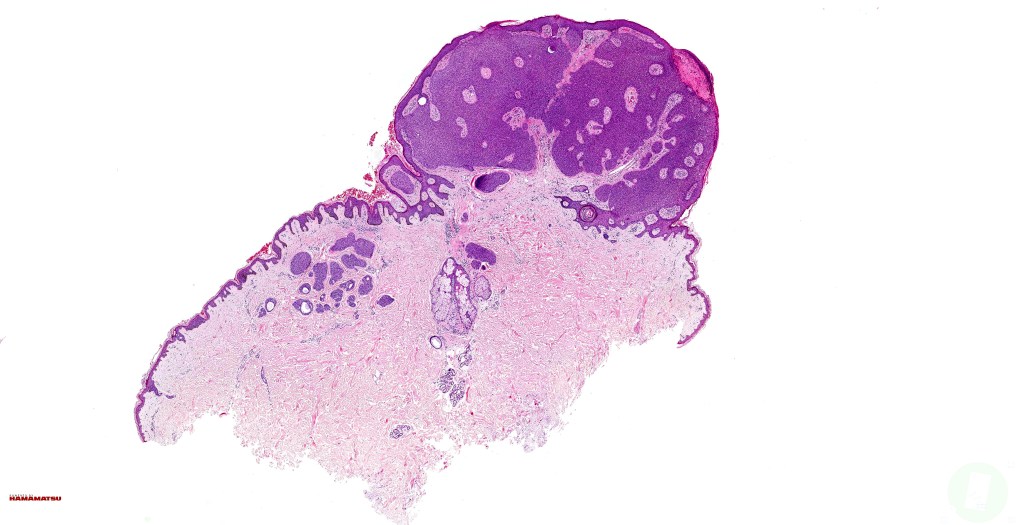

•May present as an intraepidermal lesion (hidroacanthoma simplex, a dermal tumor (dermal duct tumor) or as both with epidermal continuity (poroma); some tumors overlap hidradenoma & poroma (poroid hidradenoma overlap)

•Variably derived from the acrosyringium, the dermal duct or both

•Hidroacanthoma represents a wholly intraepidermal population of small poroid cells sharply delineated from the adjacent larger keratinocytes

•Dermal duct tumor comprises dermal nodules composed of poroid cells showing ductal differentiation & intracytoplasmic lumina with variable cyst formation

•In poroma, a dermal-centric tumor is associated with epidermal origin/continuity & is composed of small cells with vesical nuclei.